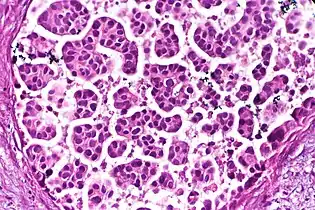

- Architectural pattern of any suspicious cells, in this case nests of cells, as well as components of the intervening stroma.

- Nests: islands of cells of similar type.

- Acinar or tubular: Each acinus consists of cells that surround a lumen.

- Cribriform: Solid with multiple clear spaces.